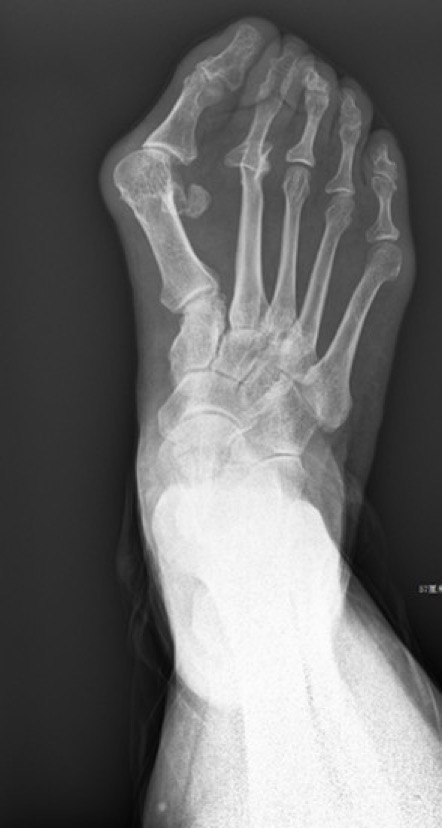

徐楚江介绍,踇外翻,俗称“大脚骨”病,简单说就是大脚趾根部的骨头,向内侧“跑偏了”,从外观看,像是多长出来了一块骨头。除了影响美观之外,更重要的是会引起大脚趾内侧疼痛、红肿,畸形形成后,难以自行矫形,局部疼痛逐渐加重,步行困难,男女比例1:9~1:15。

近日,家住广州海珠区的于女士跳完广场舞后大踇趾突然红肿疼痛,无法穿鞋行走,随即来到南方医科大学中西医结合医院找到了骨伤科徐楚江主任医师就诊。原来于女士从小就踇趾外翻,徐楚江为于女士制定了无痛微创踇外翻矫形手术治疗个性化方案,解决了困扰她30多年的足部顽疾。